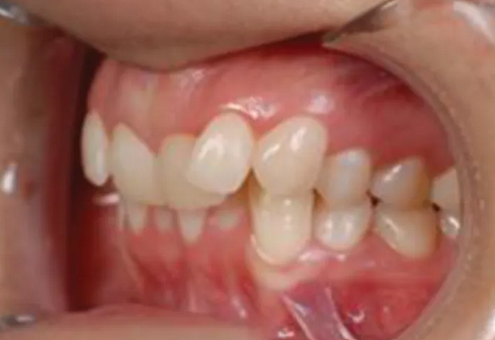

17

Q

Malocclusion is best visualized from a/an _________

A

intraoral lateral view

12

Class type

Class 2 div 2